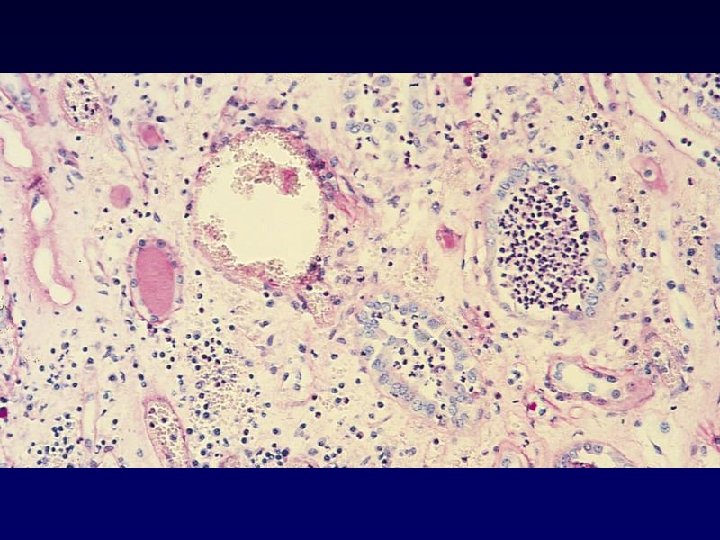

Pyelonephritis - glomerular hemorrhage